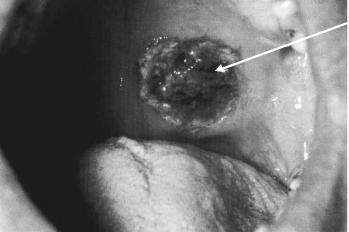

Воспаление носа и полости рта: язвы в полости рта (рис. 9-1), гнойные или кровянистые выделения из носа.

Рис 9-1. Язва в полости рта.